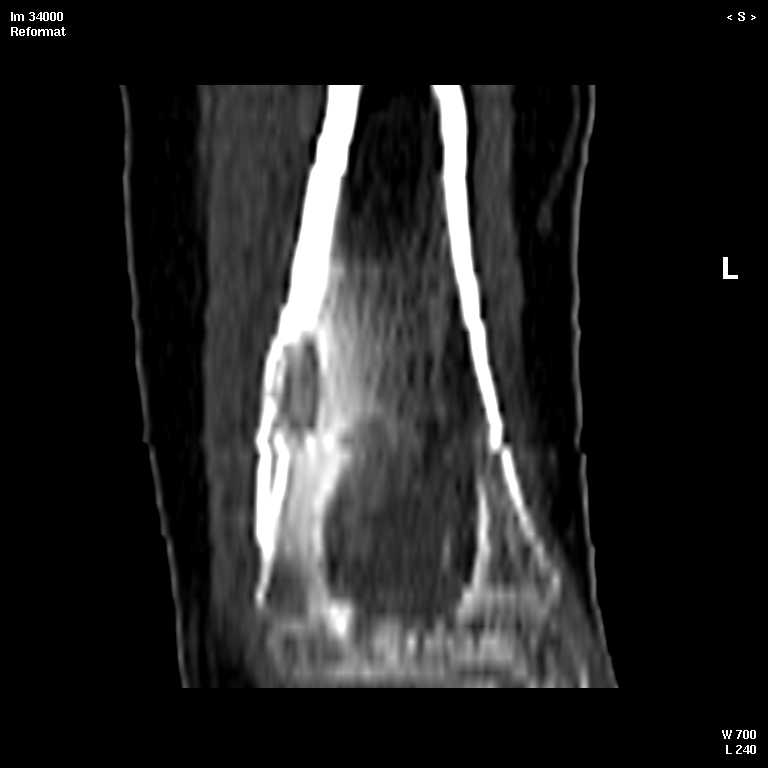

С подозрением на хондрому большеберцовой кости левой голени выполнена компьютерная томография. На серии томограмм получены изображения дистальных отделов левой голени. В дистальном метафизе на уровне нижней трети по латеральному краю определяется кортикальный очаг деструкции размерами 1,3x0,5x0,8 см. На уровне очага деструкции отмечается истончение кортикального слоя, без признаков его разрушения. Кость на уровне очага вздута. Структура окружающих мягких тканей не нарушена, объемных образований не определяется. Крупные нервные стволы и просветы крупных сосудов хорошо дифференцируются. Кожа и подкожно-жировая клетчатка не изменены.Заключение: КТ - признаки кортикального остеолитического очага деструкции в дистальном отделе метафиза левой большеберцовой кости без признаков разрушения кортикального слоя (остеогенная саркома?).19.11.2002 г. осмотрена онкологом, выставлен диагноз: саркома левой большеберцовой кости?Лабораторные исследования: - ОAK от 06.11.2002 г. - L - 11,3х109; эр. - 4,47хЮ12; НЬ - 117 гр./л; Ht - 33,6%; тр. -208x109; СОЭ - 38 мм./час, э-1; п-7; с-55; м-4; л-33.В отделении детской онкологии 11.12.02 выполнена операция: секвестр-некрэктомия н/3 левой большеберцовой кости.Послеоперационный период без осложнений.Проведено лечение. Линкомицин 150 мгхЗ р./д., обезболивание (анальгин, димедрол). Швы сняты 23.12.02, заживление первичным натяжением.Получен результат гистологического исследования: хронический остеомиелит. Данных за онкопроцесс нет.На приеме врача ортопеда поликлиники с жалобами на усиление болевого синдрома 03.01.03. Наложена задняя гипсовая лангета. Назначен противовоспалительная терапия, препараты Са и кальцийтониновые препараты. На фоне проводимого лечения болевой синдром купировался. На серии рентгенограмм (январь-февраль-март) На нижней трети левой большеберцовой кости наличие дополнительного кортикального очага диструкции с размерами 1.5x0,5 см., в динамике отмечается увеличение в размерах.С подозрением на рецидив хронического остеомиелита большеберцовой кости левой голени выполнена компьютерная томография.19/03/2003 На серии томограмм получены изображения дистальных отделов нижней трети левой голени и мягких тканей.В метафизе определяется очаг деструкции с четкими, неровными контурами, неоднородной структуры, за счет костных балок, размерами 1.8x1.8x2,4 см, плотностью 29 ед Н.В дистальном методиафизе. по латеральному краю, определяется кортикальный очаг деструкции, размерами 0,6x0,5x2,0 см, неоднородной структуры, за счет наличия фиброзных и костных балок, кортикальный слой истончен, без признаков разрушения.Структура окружающих мягких тканей не нарушена, объемных образований не определяется. Крупные нервные стволы и просветы крупных сосудов хорошо дифференцируются.Кожа и подкожно-жировая клетчатка не изменены.ЗАКЛЮЧЕНИЕ:КТ-картина состояния после операции. Формирование постоперационной, внутрикостной кисты. КТ-признаки объемного образования нижней трети левой большеберцовой кости, вероятнее всего фиброзная дисплазияРЕКОМЕНДАЦИИ: МРТ левого голеностопного сустава с захватом нижней трети голени.Лабораторные исследования: OAK от 05.03.2003 г. - L v 7.0х109; эр. - 4,74хЮ12; НЬ - 130 гр./л; Ht - 37%; тр. -274x109; СОЭ - 4 мм./час, э-1; п-1; с-53; м-3; л-42.Вопросы: уточнение диагноза? (хр.остеомиелит, обострение? Или все таки онкопроцесс) какие исследования провести? тактика лечения? КТ-снимки во вложении. Заранее благодарен!С уважением, Н.П.Козел.

Представленная томограмма напоминает остеомиеэлит метафиза большеберцовой кости с вовлечением в воспалительный процесс дистального эпифиза и зоны роста. Коль скоро после первичной обработки очага наступил рецидив необходима повторная хирургия с кюрретажом полостей и повторной гистологией и посевом материала и при этом попросить гистолога более подробно описать препарат в плане наличия или отсутствия признаков специфического воспаления (туберкулез). Наиболее частым возбудителем гематогенного остеомиеэлита в этой возрастной группе является staphilococcus aureus, но тем не менее посев материала даст более специфическую ориентировку в плане антибактериальной